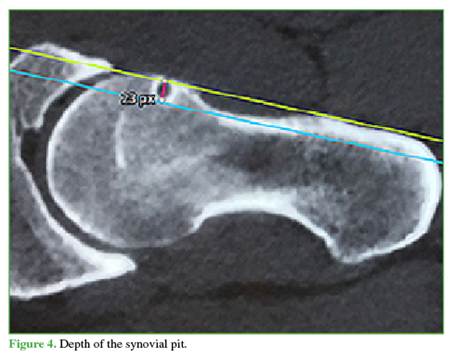

SP morphology: The following parameters were analyzed on axial oblique CT or arthro-MRI slices: 1) measured by a tangent from the anterior femoral cortex to the deepest point of the SP (Figure 4); 2) measured by a tangent from the proximal femoral border to the most distal point of the SP (Figure 5); 3) Shape: round, oval, or multilobulated; and 4) Rim: complete (cyst) or incomplete (notched).